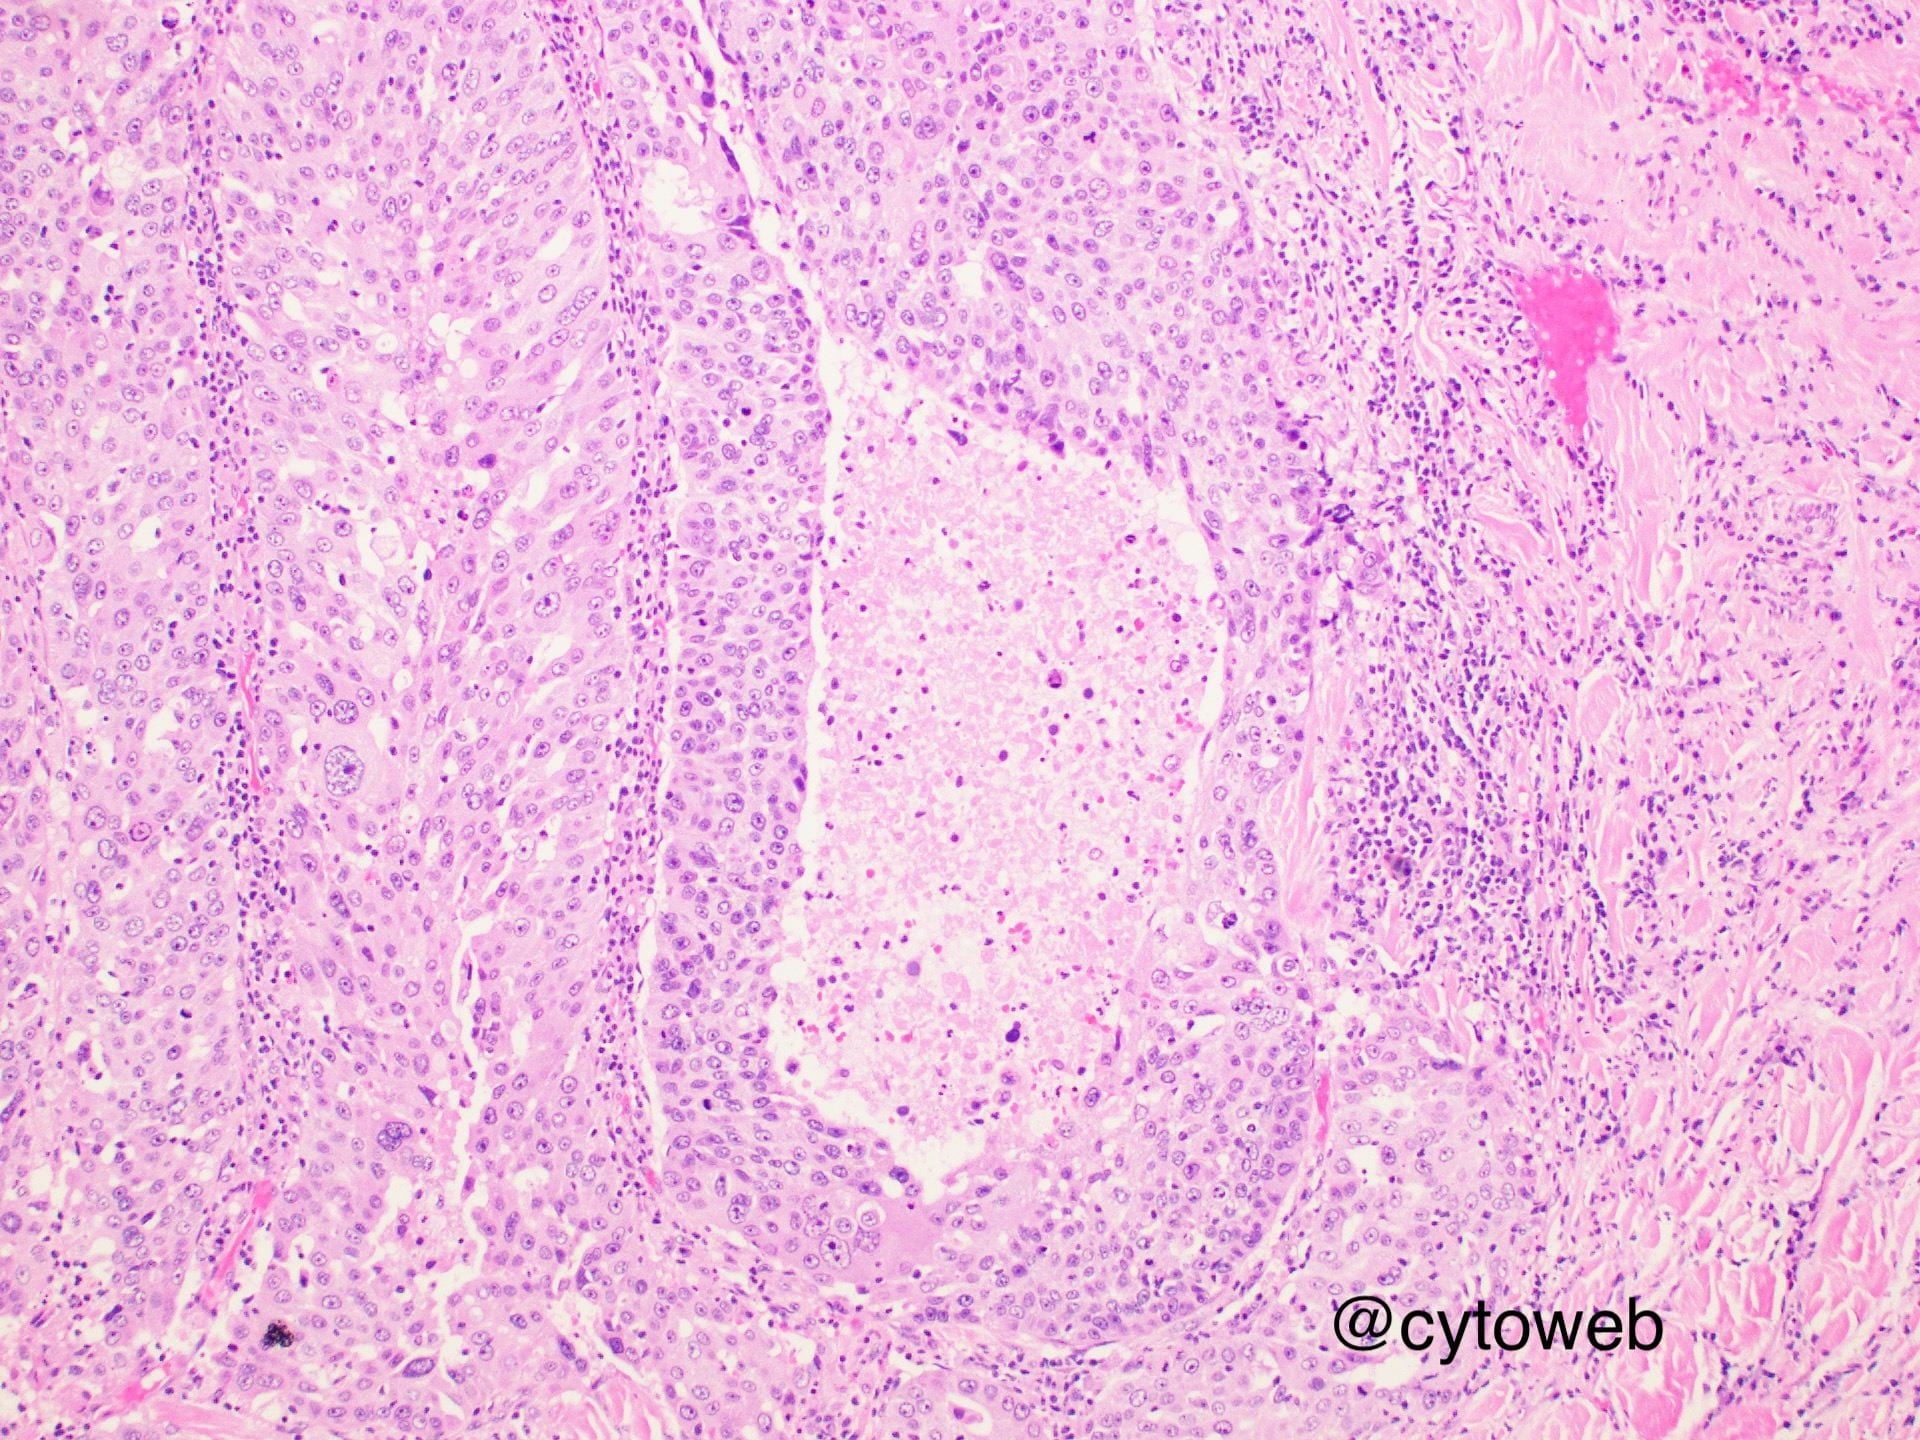

Clinical history: A 65-year-old man presented with an enlarging lump at his left jaw. FNA of the lump is performed.

Case writer: Dr Noel Chia